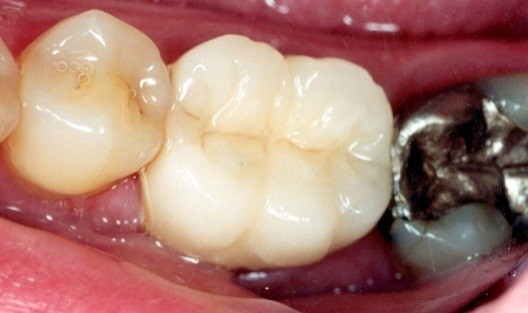

A toothache caused by a broken tooth (tooth fracture) without associated cavity or advanced gum disease. Biting on the area of tooth fracture can cause severe sharp pains. These fractures are usually due to chewing or biting hard objects such as hard candies, pencils, nuts, etc. Sometimes, the fracture can be seen by painting a special dye on the cracked tooth. Treatment usually is to protect the tooth with a crown. However, if placing a crown does not relieve pain symptoms, a root canal procedure may be necessary.